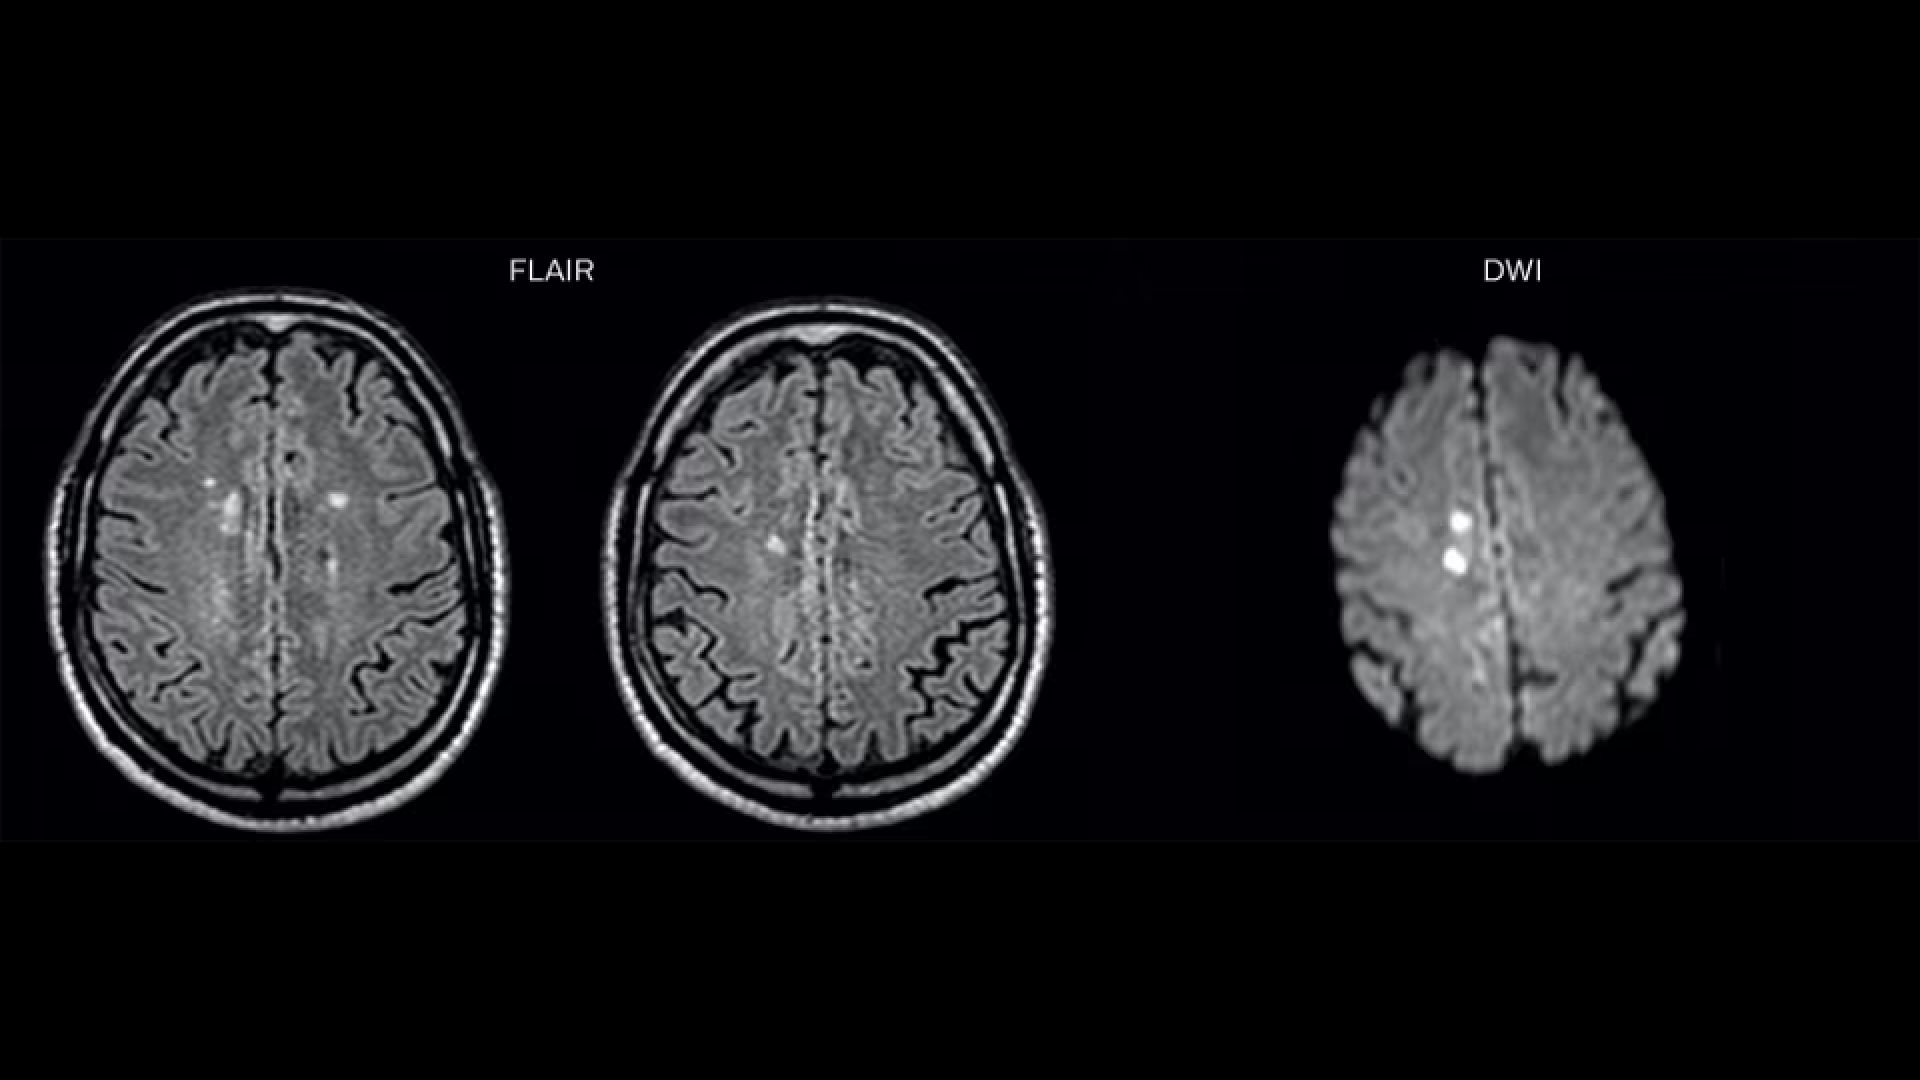

On FLAIR images we can see some nonspecific high signal abnormalities in frontal white matter bilaterally. On DWI we can see acute ischemic lesions which appear with high signal intensity. Arrows show vessel wall enhancement which appears concentric and homogeneous in different cerebral territories.

“On the routine MR sequences that we did, we could see acute ischemic lesions. We see them very well on the diffusion images, where acute ischemic lesions usually appear with high signal intensity and restricted diffusion. However, the etiology of these lesions cannot be derived from these images.

An area of restricted diffusion was seen in the anterior cerebral artery territory and we concluded it was an ischemic lesion. On MR angiography we can just see if there is stenosis or vessel occlusion, but it does not provide us information on the etiology of this kind of lesion. So, we decided to perform Black Blood imaging. The presence and the pattern of vessel wall enhancement on Black Blood imaging can help us to determine the etiology of the lesion.